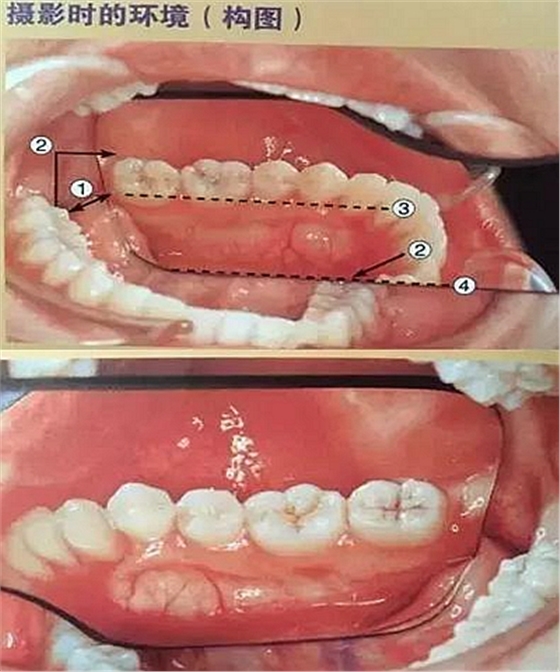

五、頰側(cè)面攝影

口腔攝影方法與技巧

①拿掉攝影側(cè)的口角拉鉤

②輕輕拉住非攝影側(cè)的口角拉鉤

③調(diào)整患者面部的方向(拍右側(cè)向右轉(zhuǎn),拍左側(cè)向左轉(zhuǎn))

④反光板遠離牙列

⑤牙列在反光板中央位置為好

⑥反光板邊緣與咬合平面平行

⑦反光板開口角度盡可能大

六、咬合面的拍攝